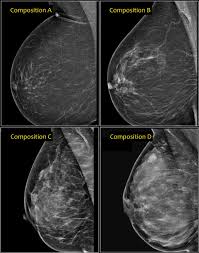

Mammography Wikipedia from upload.wikimedia.org Even if you have a lump in only one breast, pictures will be taken of both breasts. However, in rare cases, breast cancer can be the cause of gynecomastia so, a full mammographic investigation is always necessary. Dense breast tissue appears solid. 1 the gray areas correspond to normal fatty tissue, while the white areas are normal breast tissue with ducts and lobes. This overlapping tissue can cause the resulting image to look like cancer. After a mammogram that didn't show anything, and a sonogram that found the lump, i was diagnosed with stage 2 breast cancer. This is why you should always talk to your doctor if you notice an unexplained change in the size of a breast. We'll show you breast cancer pictures to help you identify any physical traits of the condition.

Essentially, mammograms turn a 3d object into a 2d object. This is why you should always talk to your doctor if you notice an unexplained change in the size of a breast. What does the doctor look for on a mammogram? cancer.org. A screening mammogram is performed at regular intervals to check for breast cancer in women who have no signs or symptoms of the disease. Bright spots on a mammogram that look like potential tumors could turn out to be overlapping tissues or a blood vessel folding over on itself, friedewald said. To license this video for patient education or content marketing, visit: What does breast cancer look like? This overlapping tissue can cause the resulting image to look like cancer. Finding breast lumps and seeing change in the size and shape. Screening mammograms have been used since the 1980s. Digital breast tomosynthesis (tomo), also known as 3d mammography, is a revolutionary new screening and diagnostic breast imaging tool to improve the early detection of breast cancer. Ultrasound characterization of breast masses. indian journal of radiology and imaging. Calcifications are calcium deposits within the breast tissue and they look like small white spots.

Moose & doc breast cancer, 21 may 2018. We'll show you breast cancer pictures to help you identify any physical traits of the condition. Normal breast tissue can look 100,000 different ways on a mammogram. Finding breast lumps and seeing change in the size and shape. Dense breast tissue appears solid. Essentially, mammograms turn a 3d object into a 2d object. American cancer society, 9 oct 2017. That makes it easy to detect abnormalities, which generally show up as white. A 3d mammogram is used to look for breast cancer in people who have no signs or symptoms. More importantly, the overlap can obscure small breast cancers. A screening mammogram is performed at regular intervals to check for breast cancer in women who have no signs or symptoms of the disease. Several patterns of calcifications are seen with dcis, including: Breast cancer and some noncancerous (benign) breast conditions can appear white on a mammogram.

More Breast Cancers Detected With 3d Mammography National Breast Cancer Foundation Nbcf Donate Online from 1o2l7w1aqqrk1f987e40vzis-wpengine.netdna-ssl.com This overlapping tissue can cause the resulting image to look like cancer. Several patterns of calcifications are seen with dcis, including: The look of breast cancer on a mammogram a tumor or lump will appear as a focused white area on the mammogram. Most screening mammograms include two views of each breast taken from different angles. Specialist doctors (radiologists) trained to interpret mammograms can identify any abnormal areas, masses or calcium. What does breast cancer look like on a mammogram? A tumor that is benign, it is not a health problem and it may not grow or change shape. Ultrasound characterization of breast masses. indian journal of radiology and imaging.

Breast cancer and some noncancerous (benign) breast conditions can appear white on a mammogram. This overlapping tissue can cause the resulting image to look like cancer. Diagnostic mammograms involve taking more views than screening mammograms. It's so important to listen to the messages our bodies are telling. A number of studies have found that 3d mammograms find more cancers than traditional 2d mammograms and also reduce the number of false positives. Ultrasound characterization of breast masses. indian journal of radiology and imaging. Even if you have a lump in only one breast, pictures will be taken of both breasts. Finding breast lumps and seeing change in the size and shape. 1 the gray areas correspond to normal fatty tissue, while the white areas are normal breast tissue with ducts and lobes. A false positive is when a mammogram shows an abnormal area that looks like a cancer but turns out to be normal. Breast cancer can appear as a spiculated mass, cluster of tiny calcifications, smoothly marginated mass, area of subtle distortion or be invisible on. Macrocalcifications, which look like small white dots on a mammogram. One advantage of ultrasound technology is that it allows substantial freedom in obtaining breast images from any orientation.